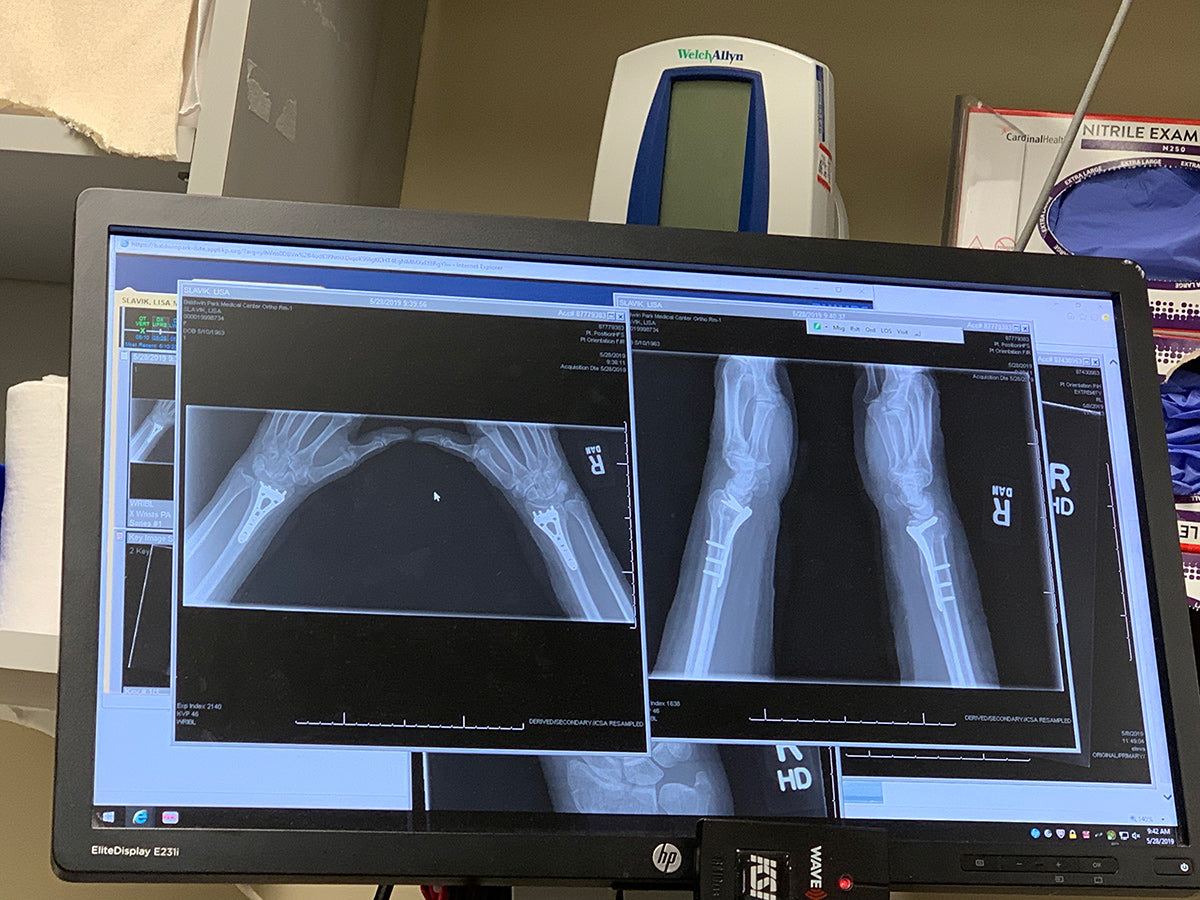

When the angels of doom (aka the orthopedic nurses) came to tell me I needed surgery I didn't cry as hard or put up a fight like when I had shattered my collarbone. I surrendered to it having already faced that fear years before. I finally got it. I had walked through the fire of fear. I am now the official Bionic Woman with plates and pins in both wrists.

Once again, I was blessed to have an amazing team at Kaiser (Baldwin Park) who took great care of me through the surgery. The surgery ended up being the easy part... it was the aftercare that was a different story. Having experienced "natural" childbirth I can honestly say this was the most horrific pain I have ever experienced in my life. There were no pain pills that worked so I ended up not taking anything other than over the counter.